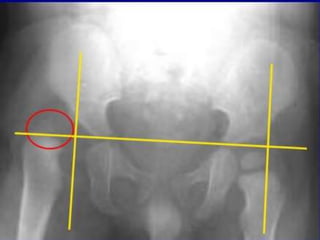

Radiologicalimaging

• X-rays